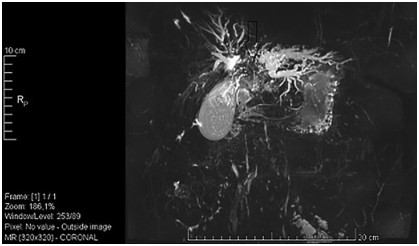

Abstract: Hilar cholangiocellular carcinoma (CCC) is a malignant neoplasm of epithelial origin occurring at the confluence of the right and left hepatic bile ducts. Typically, these tumors are small, poorly differentiated, exhibit aggressive biologic behavior with non-specific symptoms and tend to obstruct the intrahepatic bile ducts. Surgery is the only available curative option. Unfortunately, in less than half of the patients a complete resection is possible with poor survival rate in unresectable cases. In this report, we present the case of a 58-year-old woman with a history of unresectable hilar cholangiocarcinoma. Initially she was treated with intraductal dilatation of malignancy and placement of a plastic stent and chemotherapy (Gemcitabin® and Platinol®). Two years later she underwent a second-line chemotherapy with Gemcitabin® and Oxyplatin® because of tumor progression. Despite a second line chemotherapy and placement of an uncovered self-expandible metal stent (ucSEMS) that was extended later on by stent-in stent technique, there was tumor progression which led to a complex course with relapsing obstructive cholangiosepsis and cholestasis. Because of tumor ingrowth, endobiliary radiofrequency ablation of the malignant stenosis was performed in repeated sessions. This case illustrates that radiofrequency ablation of solitary malignant biliary obstruction is feasible, safe and allows an improvement of quality of life in non-operable patients.